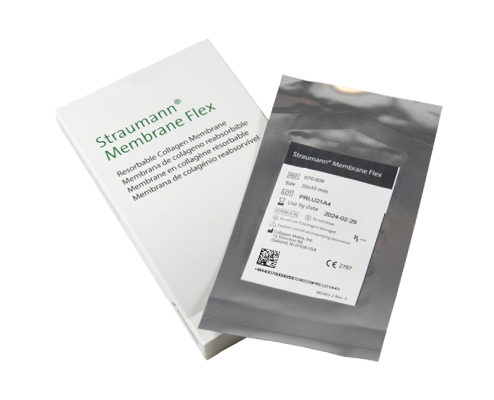

Size (mm)

15*20mm / 20*30mm / 30*40mm

Size (mm)

15*20mm / 20*30mm / 30*40mm

Predictable & controlled resorption

Protects the graft area from unwanted soft tissue infiltration

during the initial phase of healing.

Resorbs predictably over 3 to 4 months as new host collagen is

simultaneously regenerated.

during the initial phase of healing.

Resorbs predictably over 3 to 4 months as new host collagen is

simultaneously regenerated.

Highly purified porcine peritoneum and minimal crosslinking

The intact tissue of porcine peritoneum provides inherent strength

which is further minimally crosslinked,

leading to predictable resorption

and desirable handling characteristics.

which is further minimally crosslinked,

leading to predictable resorption

and desirable handling characteristics.

Predictable & controlled resorption

Protects the graft area from unwanted soft tissue infiltration

during the initial phase of healing.

Resorbs predictably over 3 to 4 months as new host collagen is

simultaneously regenerated.

during the initial phase of healing.

Resorbs predictably over 3 to 4 months as new host collagen is

simultaneously regenerated.

Highly purified porcine peritoneum and minimal crosslinking

The intact tissue of porcine peritoneum provides inherent strength

which is further minimally crosslinked,

leading to predictable resorption

and desirable handling characteristics.

which is further minimally crosslinked,

leading to predictable resorption

and desirable handling characteristics.